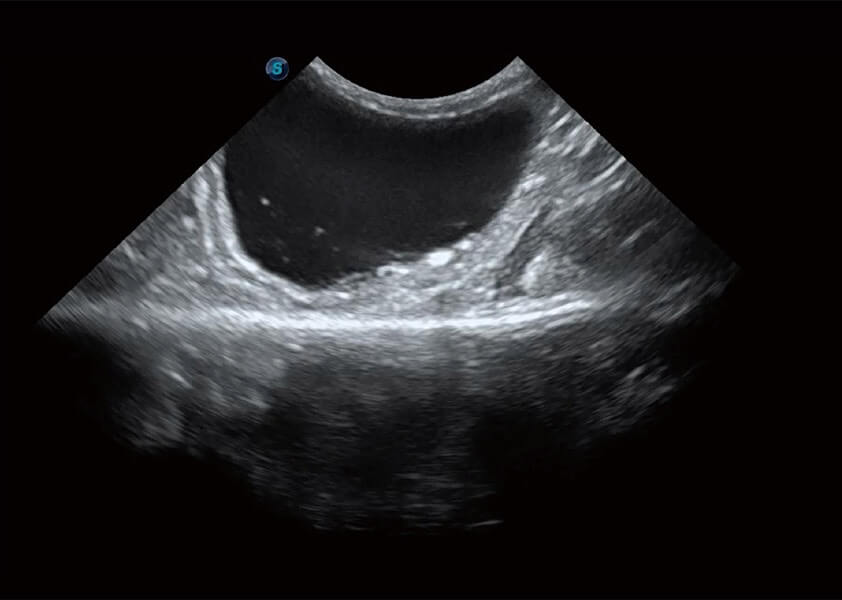

ProPet 60 作为一款高端台式动物超声设备,为动物医生的日常诊断提供了一系列贴合动物临床需求、解决临床实际问题的高级成像功能。凭借全系列高清探头,满足医生对腹部、心脏、生殖、浅表、肌骨等成像的所有需求,切实帮助您提升检查效率,提高诊断信心。

动物是人类最亲密的朋友和最值得信赖的伙伴。DB中国旗舰官方网站也一直致力于探索动物专用的超声影像解决方案。 全新推出的ProPet系列,是DB中国旗舰官方网站在动物超声影像智能化、专业化、精准化的一次跨越式革新。动物不能用言语来表述自己的不适,通过超声影像,ProPet系列搭建了动物医生与不同物种沟通的“桥梁”,为动物医生注入了“治愈之力”。